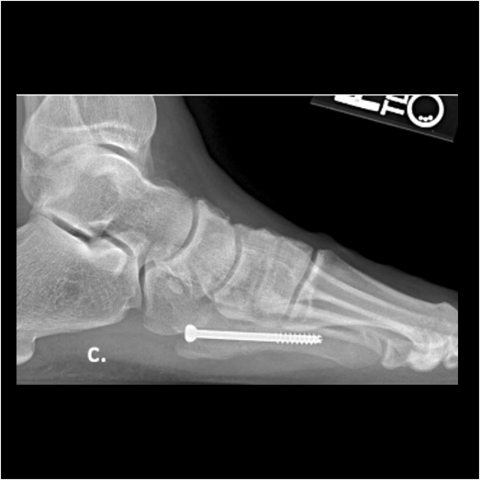

Figure 5c

Figure 5c. The 24-year-old required hardware removal and application of external fixation for gradual compression. Most cases heal within 6 weeks with gradual compression weekly.